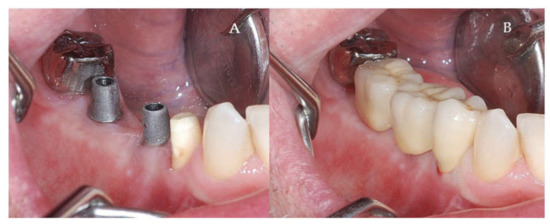

Clinical and CBCT aspects of patient from the test group, describing the stages of S-GBR technique and implant-prosthetic stage, are presented in Figure 1, Figure 2, Figure 3, Figure 4, Figure 5, Figure 6, Figure 7, Figure 8, Figure 9, Figure 10 and Figure 11. CBCT exam allows the evaluation of the horizontal alveolar bone defect and the position of the mandibular alveolar nerf (Figure 1A,B). Figure 1C,D show cross-sectional CBCT aspects of the implant sites. Figure 2 shows the narrowed mandibular alveolar bone with horizontal resorption. Figure 3 shows the exposed buccal surface of the alveolar ridge with severe horizontal resorption, after flap opening. The inserted implants (4.5 mm diameter, 11.5 mm length) and osteosynthesis screws (45° from the occlusal plan) are shown in Figure 4A. The placement of graft (autologous bone and xenograft) and collagen membrane is shown in Figure 4B. Figure 5A shows tension-free sutures, due to periosteal incisions alveolar ridge. Figure 5B shows clinical aspect at 7 months after surgery, with gingival tissue adherent on the reconstructed alveolar ridge. Figure 6 shows OPG aspect at follow-up of 7 months, with osseointegration of the dental implants. Figure 7A shows clinical aspect before osteosynthesis screws removal. Figure 7B shows clinical aspect after osteosynthesis screws removal. Figure 8A shows healthy peri-implant soft tissues. Figure 8B shows repositioning key for perfect position of abutments. Figure 10A,B show clinical aspects of implant-supported prosthetic restoration. Figure 11A,B show CBCT aspects of Osseo integrated dental implants at 24 months follow-up.

Figure 8.

(A,B) Clinical aspects at the second stage surgical session. (A) Aspect before screw removal. (B) Aspect after screw removal.

Figure 9.

(A,B) Post-operative clinical aspects 3 weeks after second stage surgery. (A) Healthy peri-implant soft tissues (B) The repositioning key of abutments.